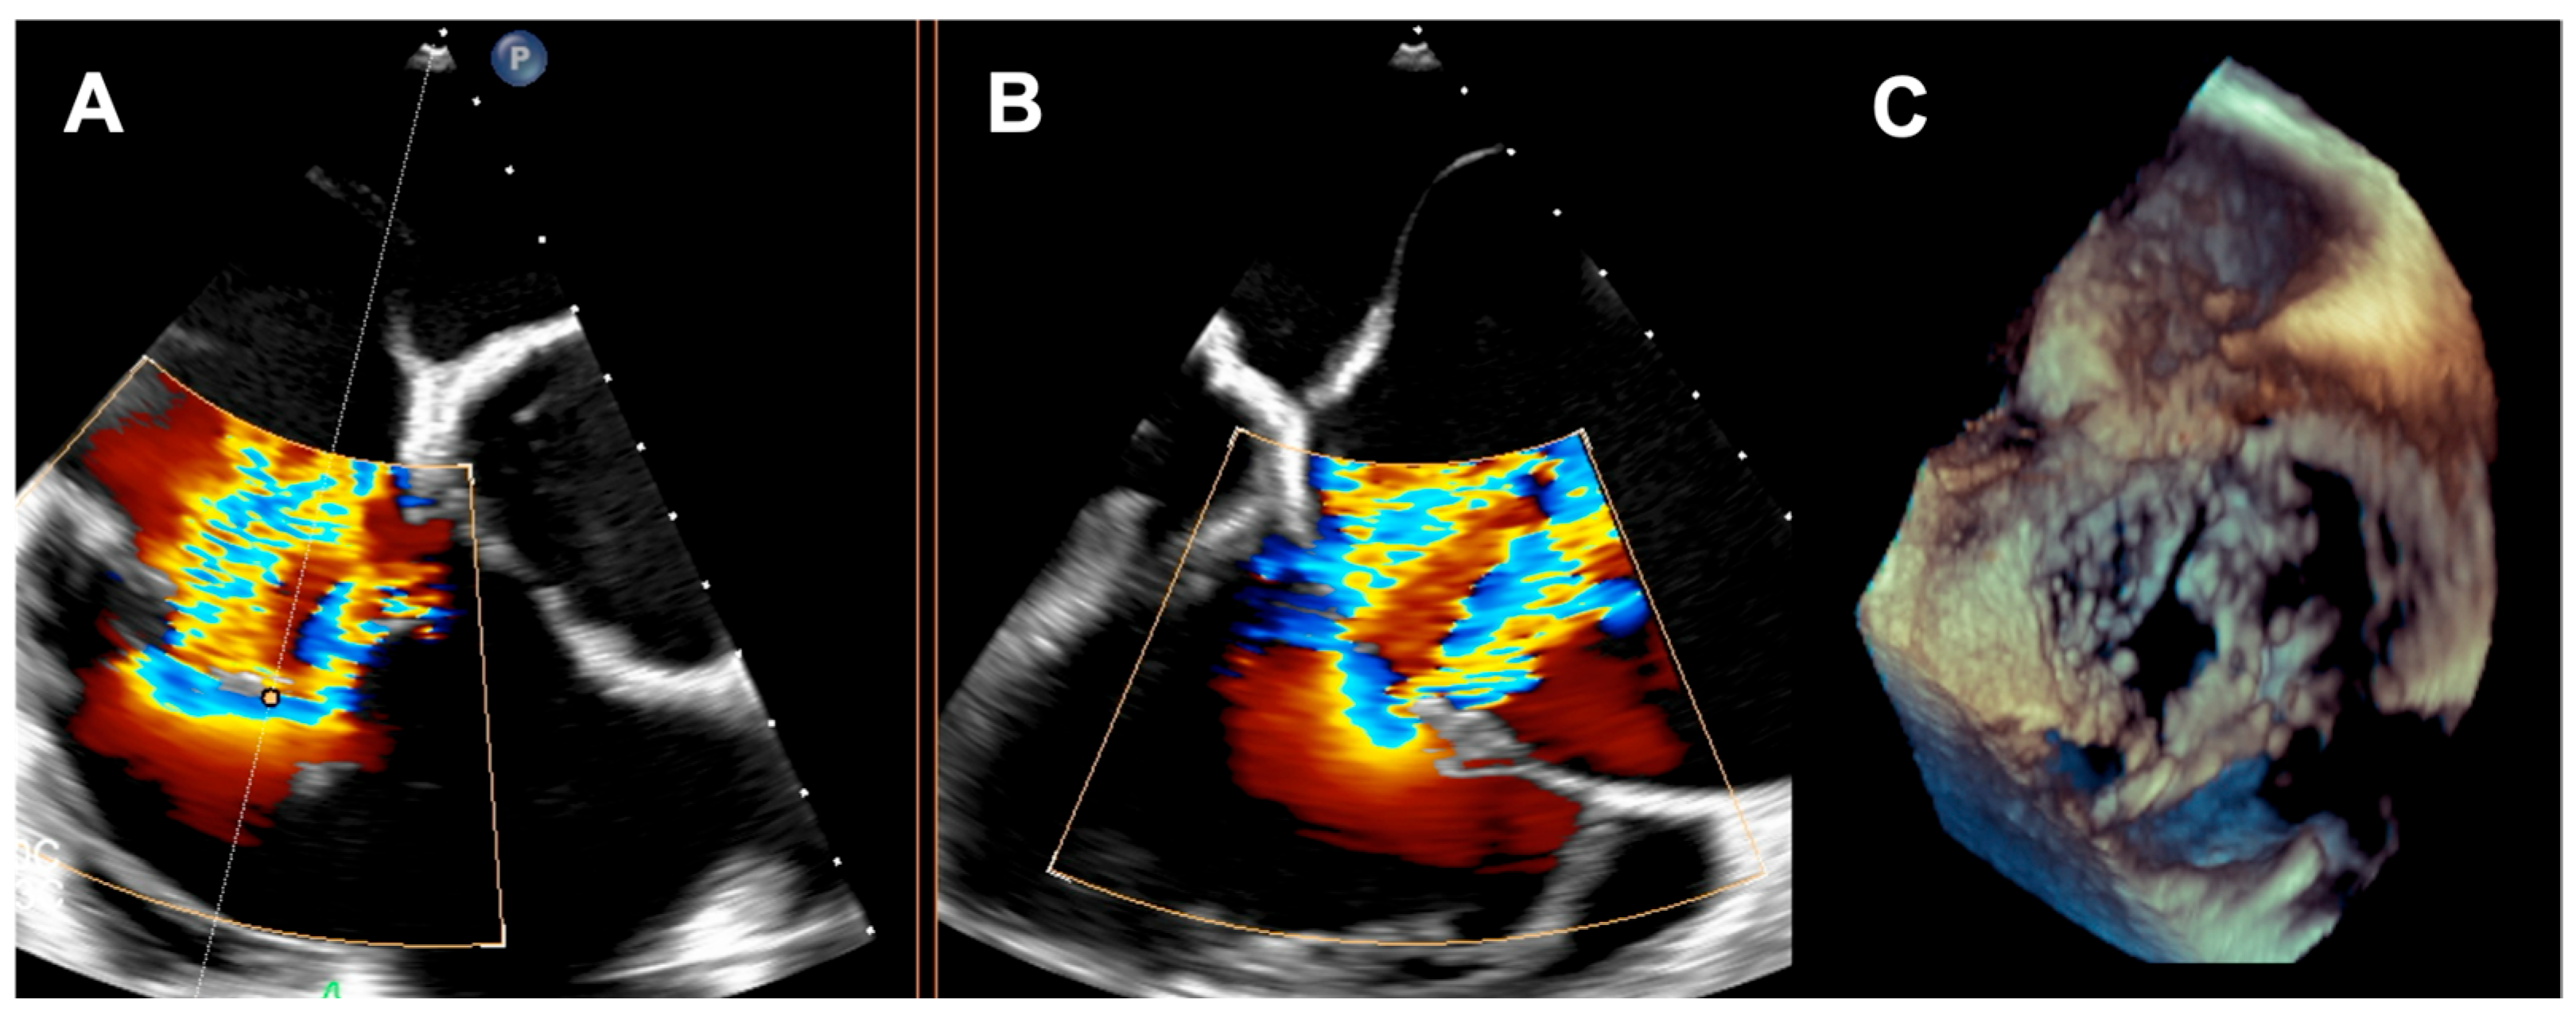

A 73-year-old woman with a history of two surgical interventions—an aortic valve replacement 25 years before and a thoracic aortic aneurysm repair 12 years before—was admitted to the hospital because of persistent heart failure symptoms in functional class NYHA III, accompanied by peripheral edema and ascites. The transthoracic echocardiography showed preserved function of the mechanical aortic prosthesis and torrential TR with tricuspid anulus enlargement. A further transesophageal examination revealed a large, mainly central coaptation deficit between the tricuspid leaflets, located mainly in the central region of the valve (Figure 3). Furthermore, a patent foramen ovale (PFO) with spontaneous right-to-left shunt was also diagnosed. Due to the valve anatomy, the patient was not deemed eligible for the transcatheter edge-to-edge repair. Because of the symptoms’ persistence, a two-step percutaneous procedure was planned. First, the PFO was closed with the 25 mm Amplazer occluder. Two weeks later, the CAVI procedure with the implantation of TricValve system valves (SVC 29 mm; IVC 45 mm) was carried out without complications. (Figure 4) We believed that the PFO closure was necessary before the CAVI procedure because the implantation of venae cavae valves in a patient with a patent PFO would have caused an exacerbation of the right-to-left shunt and possible patient desaturation. In observation, six and twelve months after the procedure, the patient remained on stable doses of oral diuretics and was considered to be in NYHA functional class II, without worsening heart failure or requiring hospitalization.

Figure 3. (A,B) Torrential tricuspid regurgitation in the RV inflow—outflow tract X-plane view; (C) large central coaptation deficit in 3D view. RV—right ventricle.